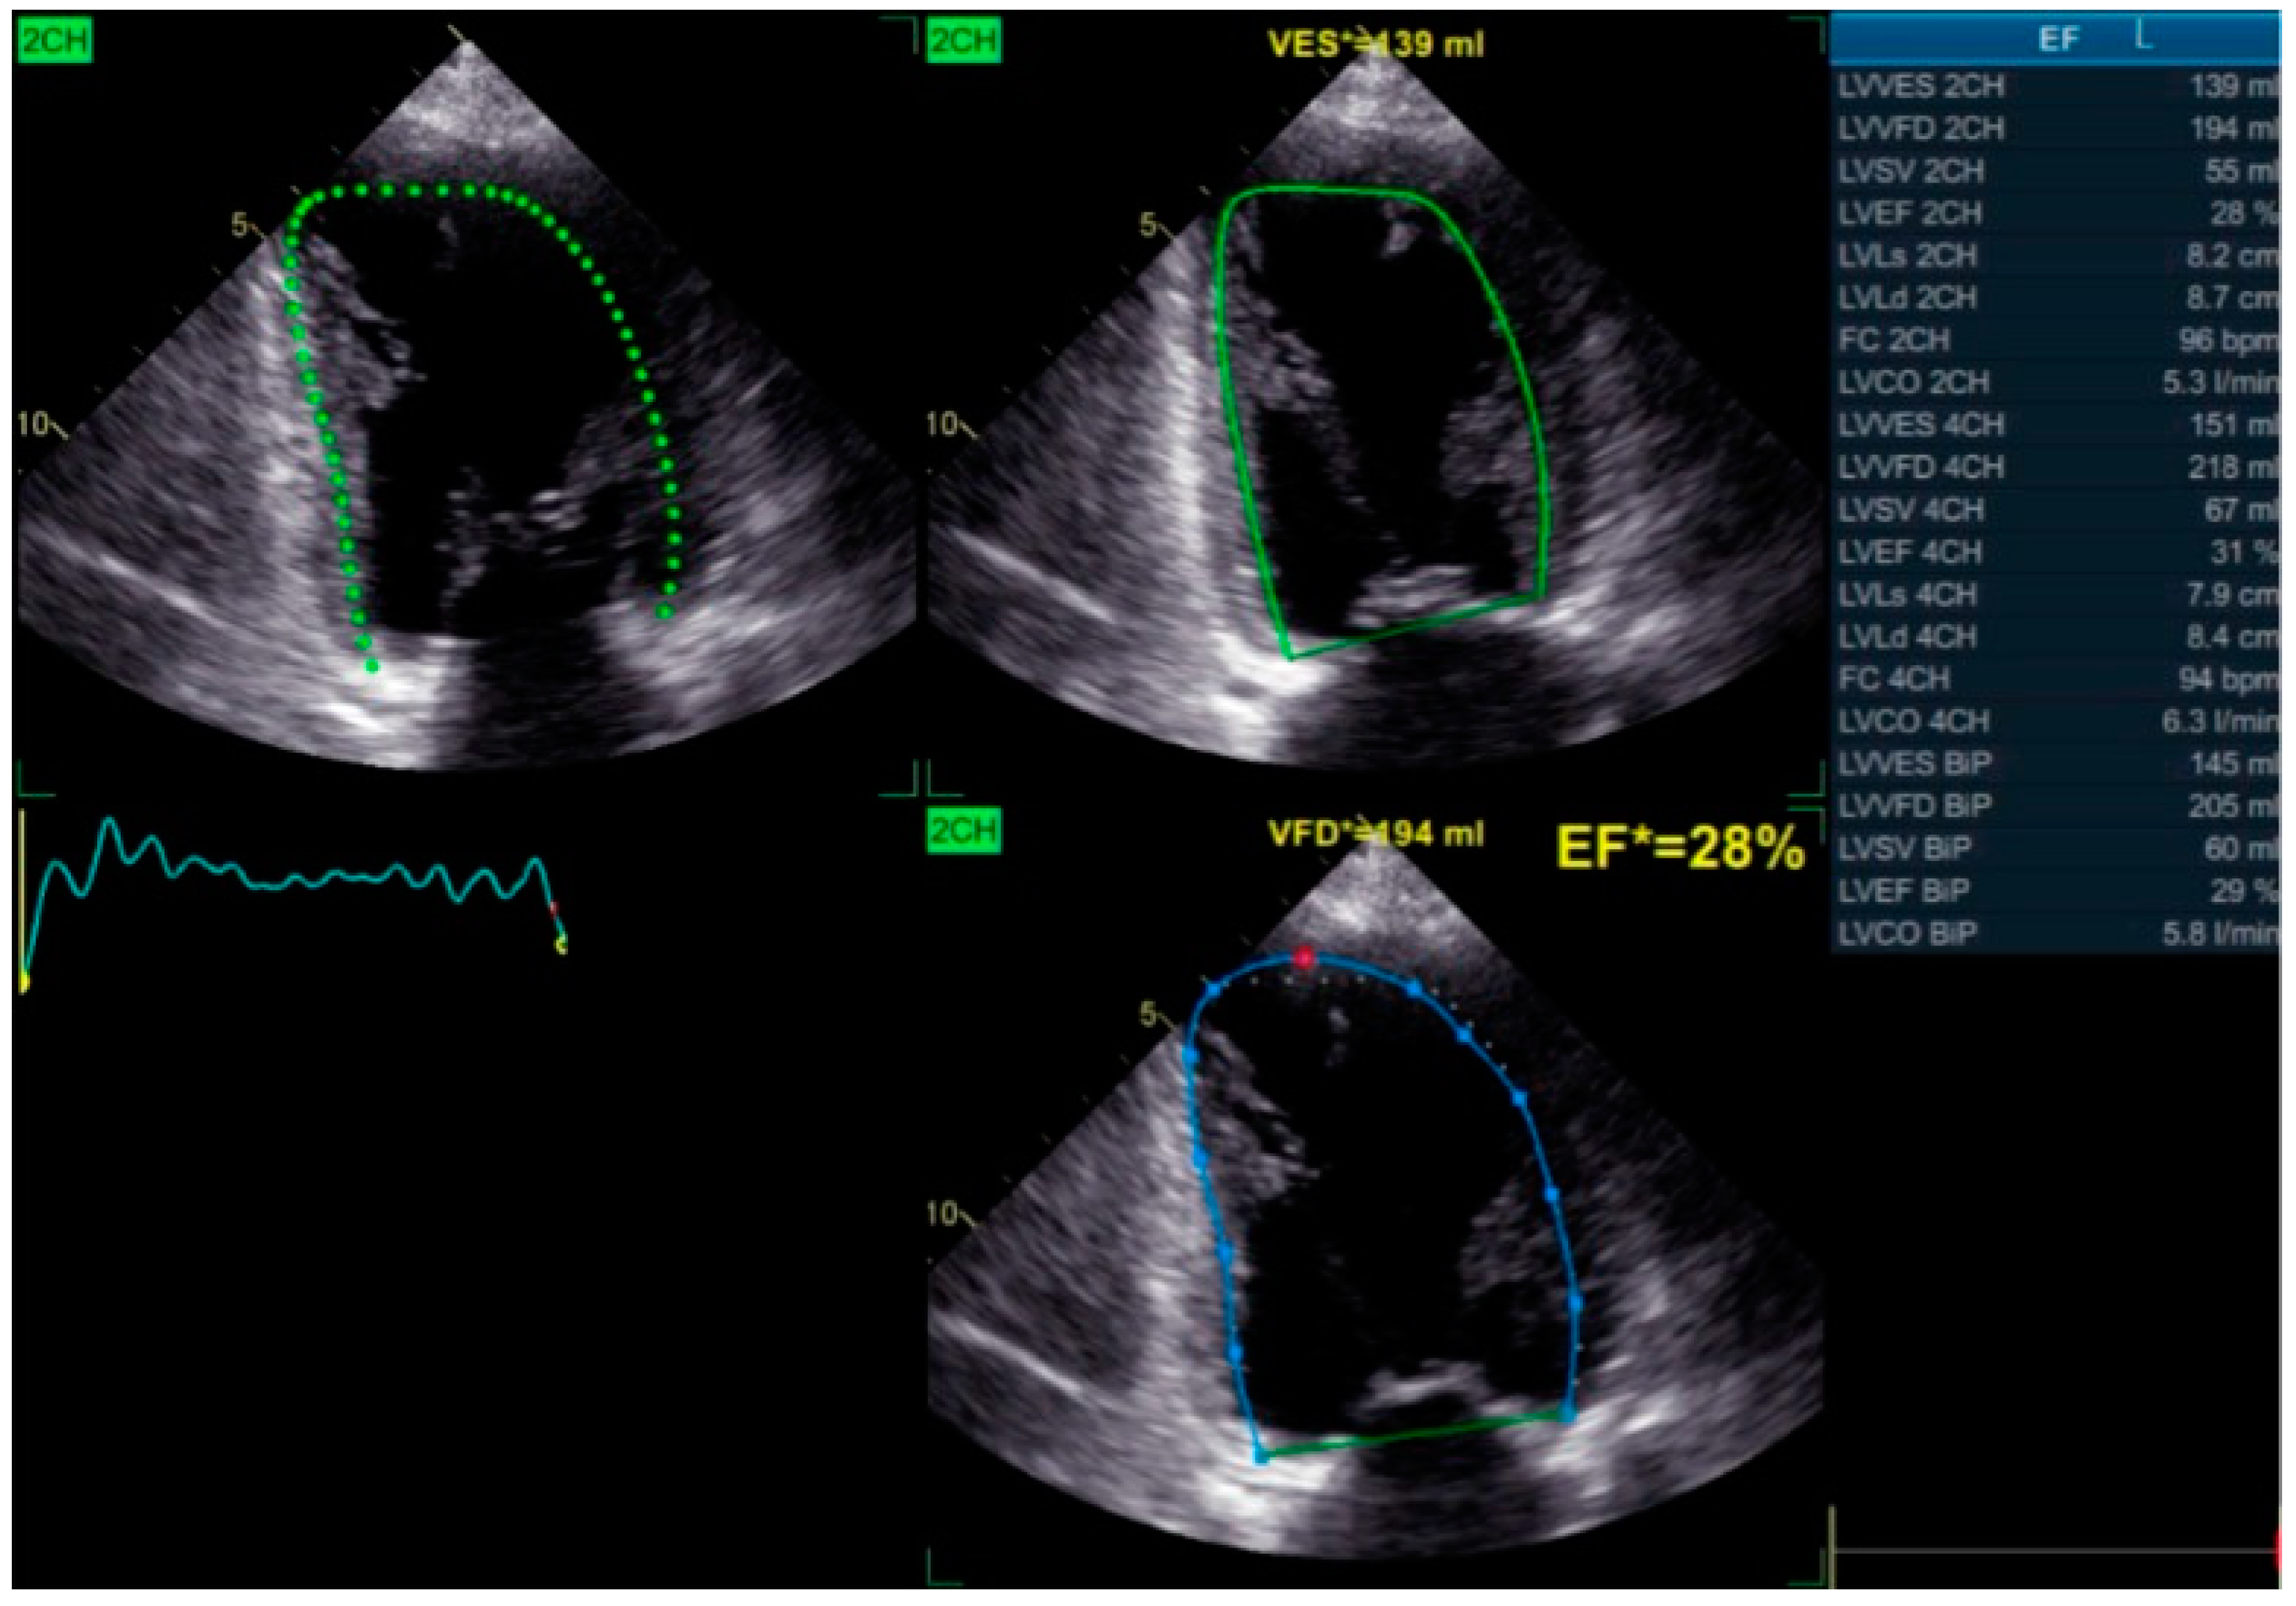

Simpson’s Method for Ejection Fraction Assessment: The biplane method of discs, or Simpson’s method, remains a cornerstone for evaluating global LV function, particularly left ventricular ejection fraction (LVEF). This technique calculates LVEF based on end-diastolic and end-systolic volumes obtained from apical two- and four-chamber views (Figure 6).

In patients with LBBB, LVEF is frequently reduced due to inefficient contraction patterns. While Simpson’s method is less sensitive than TDI or STE in detecting regional dyssynchrony, it remains essential for assessing overall ventricular performance. Declining LVEF reflects adverse remodeling, whereas improvements following BBP or CRT indicate successful resynchronization and enhanced cardiac function.

Figure 6. Biplane Simpson’s method echocardiographic assessment showing a reduced ejection fraction, indicating severe left ventricular systolic dysfunction.